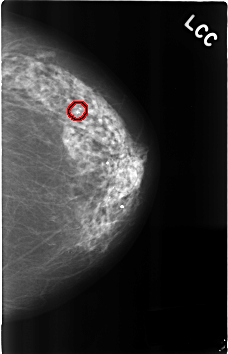

ics_version 1.0 filename C-0287-1 DATE_OF_STUDY 9 1 1995 PATIENT_AGE 89 FILM FILM_TYPE REGULAR DENSITY 2 DATE_DIGITIZED 4 8 1998 DIGITIZER LUMISYS LASER SEQUENCE LEFT_CC LINES 4592 PIXELS_PER_LINE 2960 BITS_PER_PIXEL 12 RESOLUTION 50 OVERLAY LEFT_MLO LINES 4584 PIXELS_PER_LINE 2976 BITS_PER_PIXEL 12 RESOLUTION 50 OVERLAY RIGHT_CC LINES 4568 PIXELS_PER_LINE 2928 BITS_PER_PIXEL 12 RESOLUTION 50 NON_OVERLAY RIGHT_MLO LINES 4600 PIXELS_PER_LINE 2904 BITS_PER_PIXEL 12 RESOLUTION 50 NON_OVERLAY |

FILE: C_0287_1.LEFT_CC.OVERLAY TOTAL_ABNORMALITIES 1 ABNORMALITY 1 LESION_TYPE CALCIFICATION TYPE PLEOMORPHIC DISTRIBUTION CLUSTERED ASSESSMENT 4 SUBTLETY 5 PATHOLOGY BENIGN TOTAL_OUTLINES 1 BOUNDARY |